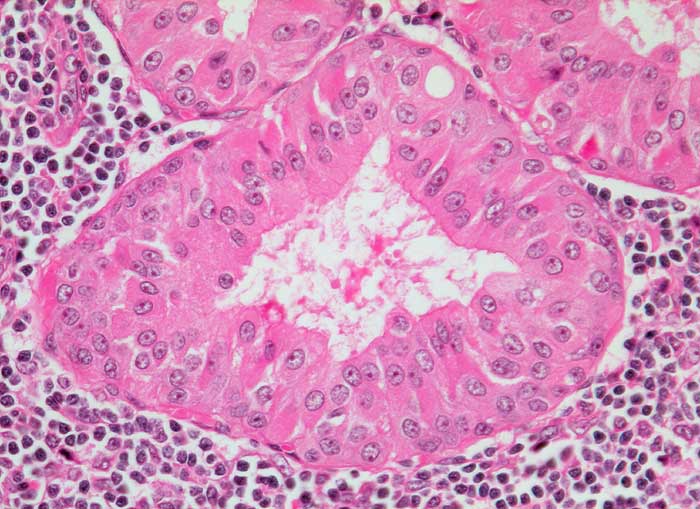

PathoPic ID 5452 - Warthin Tumor

Warthin Tumor

benigner Tumor

Parotis

Kopf & Hals, Sinnesorgane

Onkozytäre Zellen kleiden drüsenartige Hohlräume aus und sind von einem dichten lymphozytären Infiltrat umgeben.

Unklare Schwellung Parotisunterpol

Histologie

320